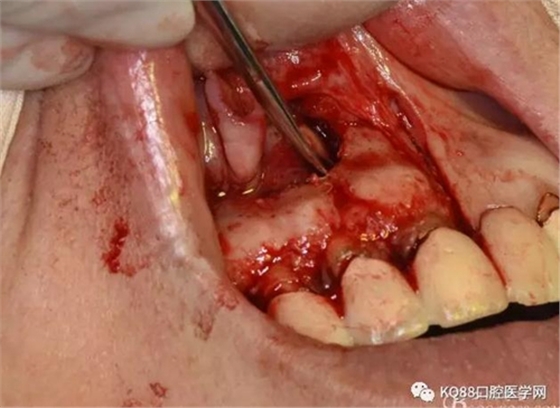

圖9.去除唇側(cè)薄的骨壁,暴露出囊壁

圖10.剝離囊壁